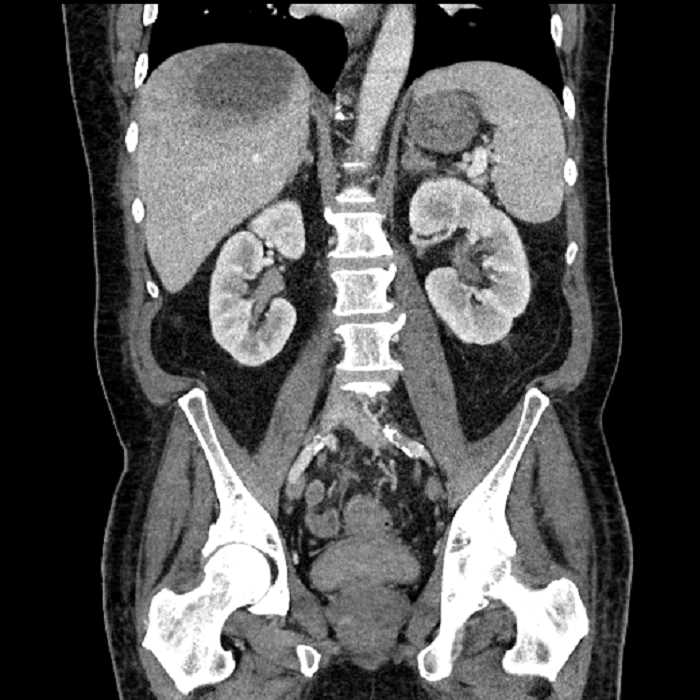

• Large fluid density structure in hepatic segments 7 and 8 measuring 10 x 7 x 7 cm with internal septation and circumferential ill-defined low density compatible with edema

• Peripherally enhancing subcapsular collections along the anterior margin of the left hepatic lobe measuring 3 x 1 cm and 2 x 1 cm

• Clearly marginated fluid density structure in segment 7 and several other scattered tiny hypodensities, which likely represent cysts

• High grade stenosis of the left common iliac artery, with the left internal and external iliac arteries remaining patent

• Incidental splenule

Acute sigmoid diverticulitis complicated by a small contained perforation and a large abscess in the right hepatic lobe. Additional small subcapsular abscesses along the anterior margin of the left hepatic lobe.

Additionally, loss of the normal fat plane between the peridiverticular collection and adjacent thickened loops of small bowel raises the potential for an enterocolonic fistula.

High grade stenosis of the left common iliac artery. The left external and internal iliac arteries are patent.